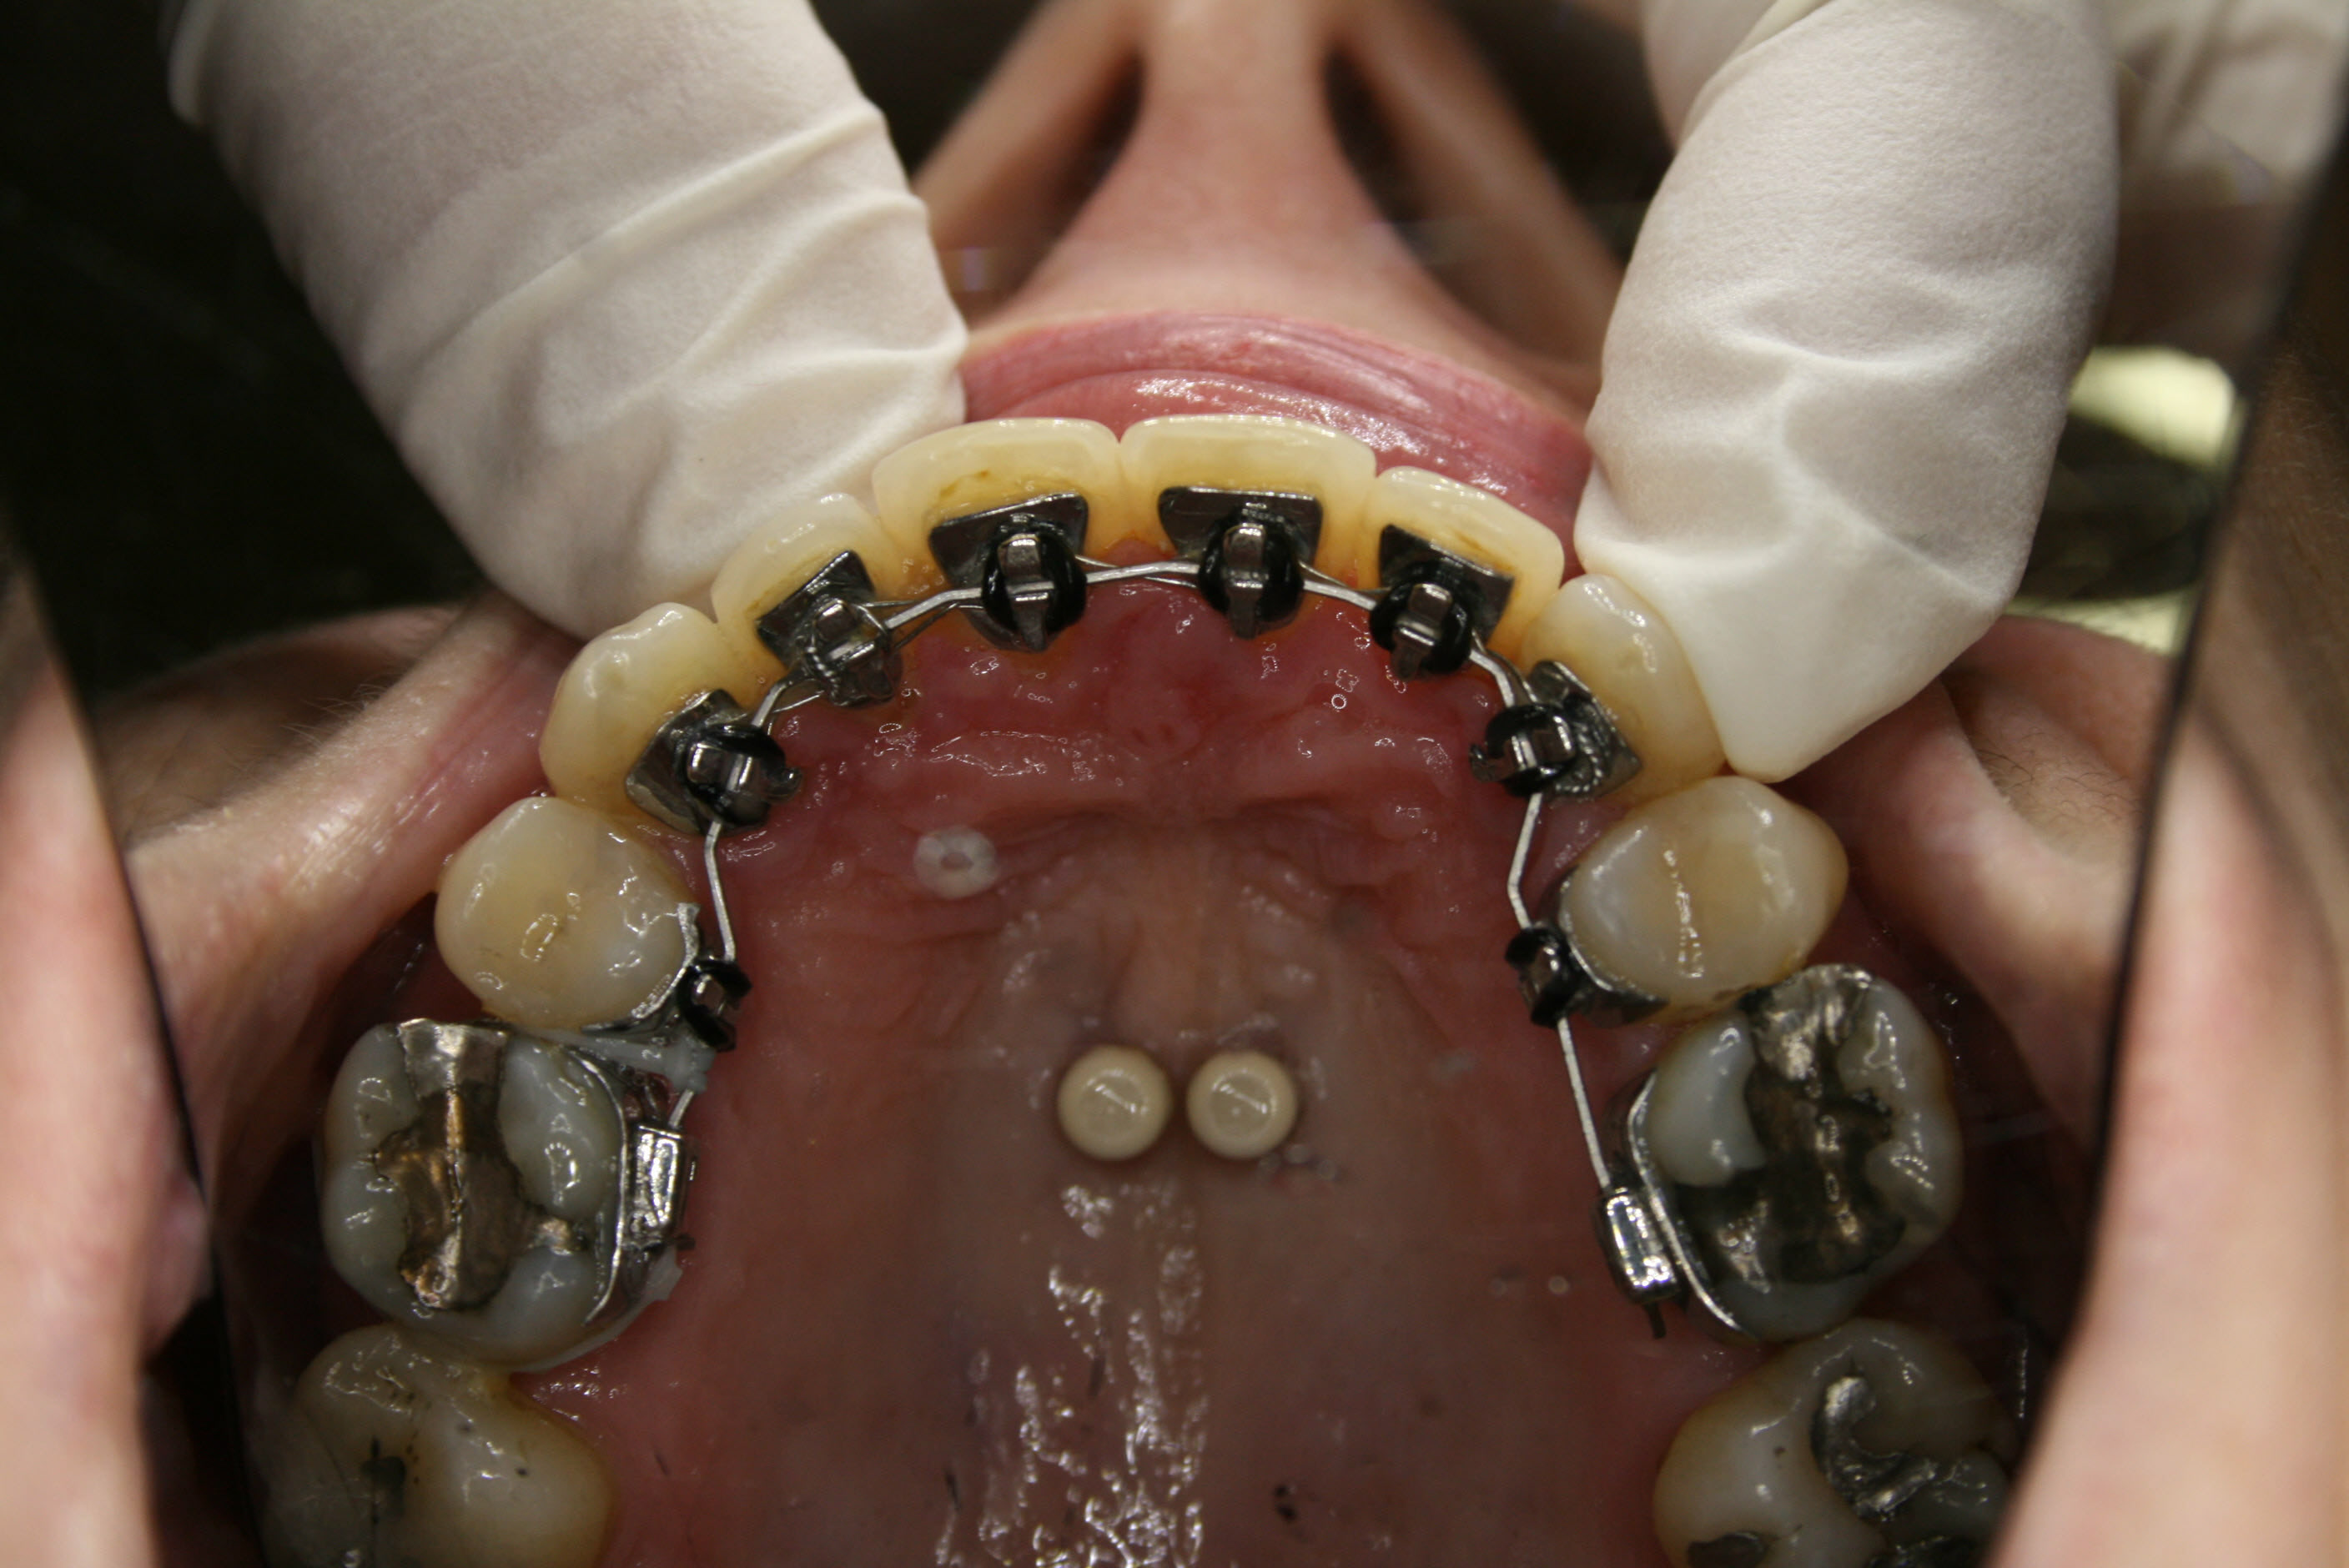

Während der Behandlung

Die ersten kleinen Backenzähne sind bereits entfernt und die festsitzende Zahnspange ist eingesetzt, in diesem Falle quasi unsichtbar auf der Innenseite der oberen Schneidezähne. Es ist wesentlich, daß die Lücken nur von vorne her geschlossen werden. Dies wurde sichergestellt, indem die Zähne hinter den Lücken über temporäre kleine Implantate am Gaumendach verankert wurden. In der Bildsequenz ist der Behandlungsfortschritt zu erkennen; der Lückenschluß war nach 1½ Jahren erreicht.